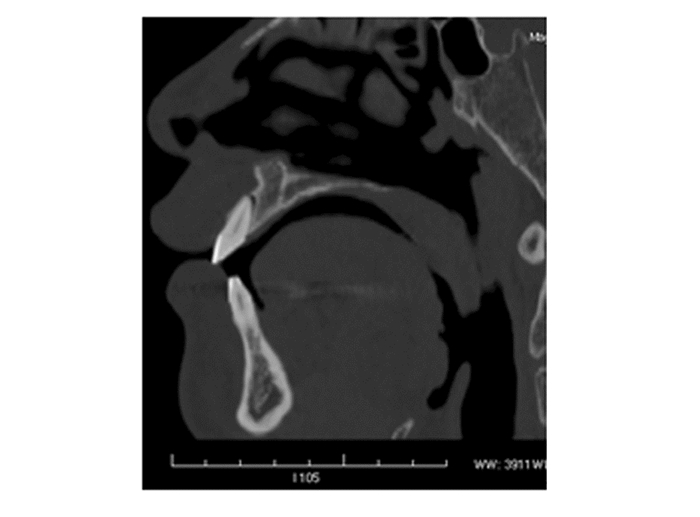

创伤性恒切牙不全脱位口腔全景和ct表现对比分析